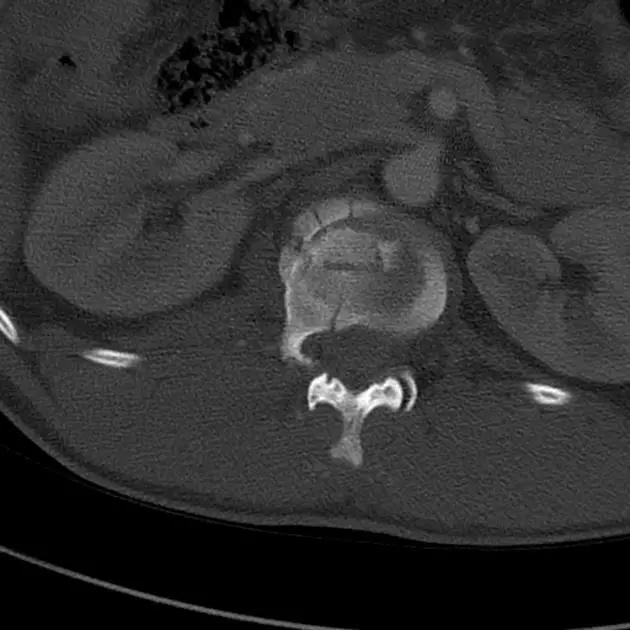

Cedell 骨折的 CT 片 (来源:Fracture of the posterior medial tubercle of the talus :A case report and review of the literature. Acta Orthop. Belg., 2007, 73, 804-806)